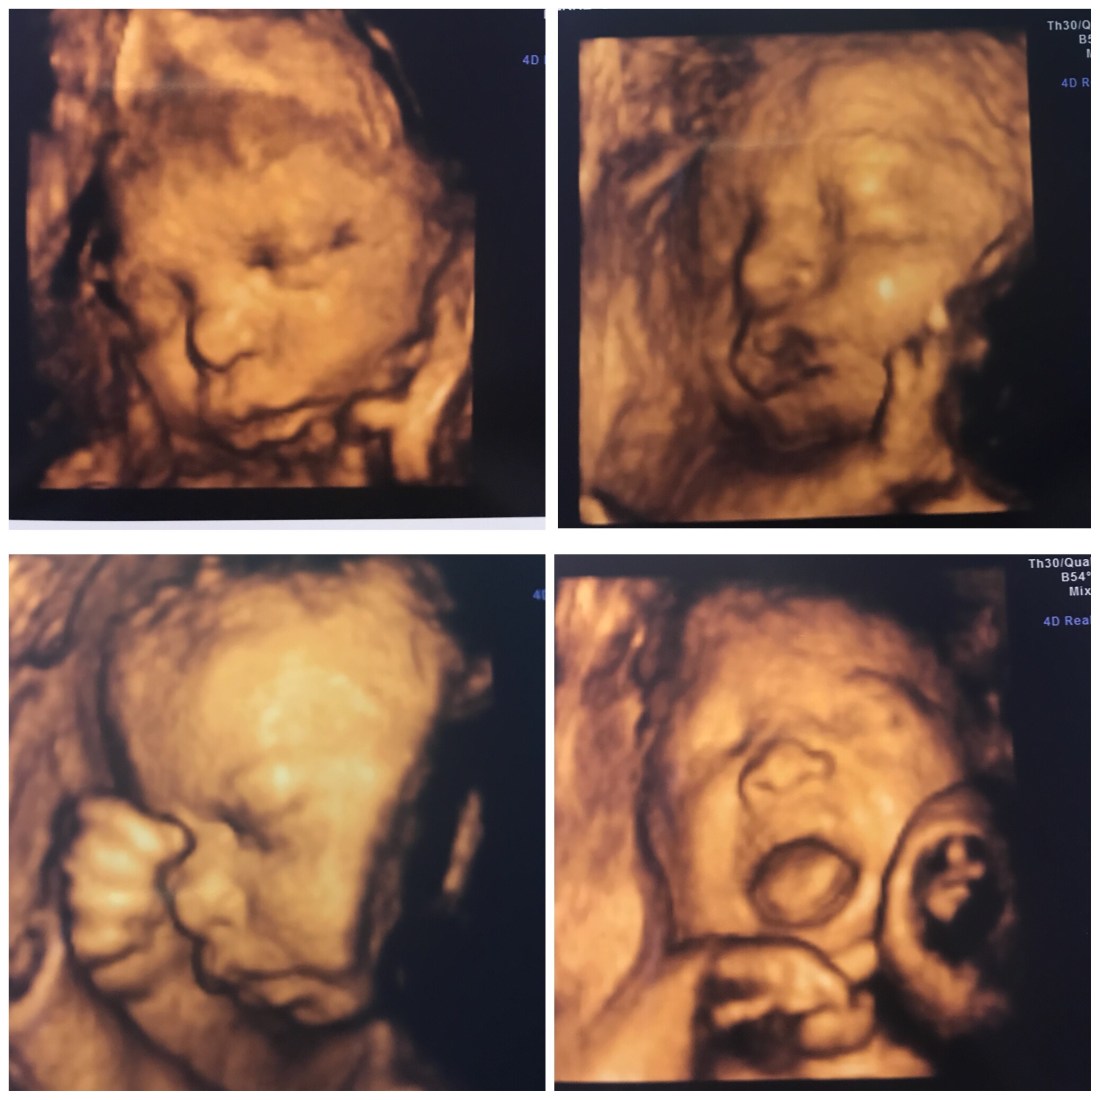

My OB called to share some incredible news with us. All test results were NORMAL. We were the soon-to-be parents of yet another healthy baby GIRL! Hank told me he prayed for another girl. We were all thrilled!